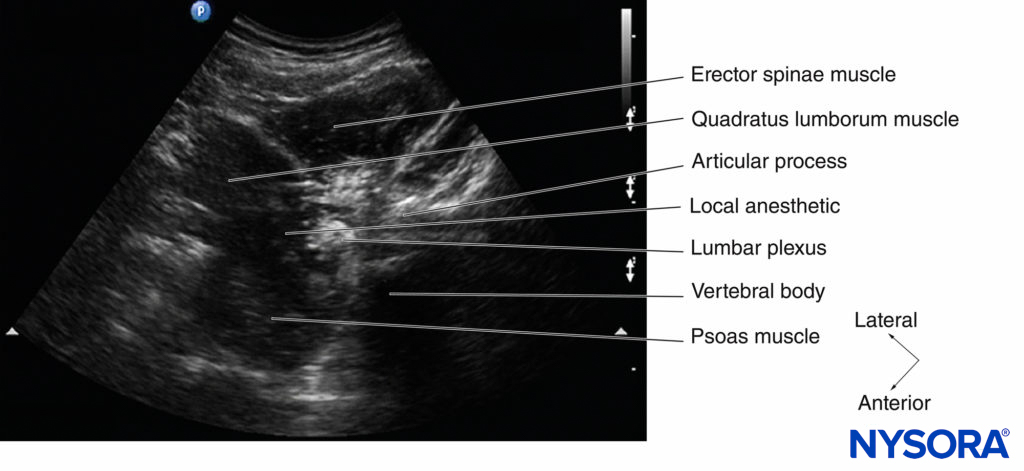

Originally described by Kirchmair and colleagues in cadavers, this technique involves performing a transverse scan of the lumbar paravertebral region to delineate the psoas major muscle (as described above) at the L3–L4 or L4–L5 level. It may be difficult to locate the psoas muscle at the L4–L5 level as the iliac crest interferes with transducer placement, particularly curved array transducers with a large footprint (60 mm). As described above, the author prefers to perform a PMTOS-AP with the patient positioned in the lateral position (Figure 23) since it provides better visualization of the anatomy relevant for LPB. Once an optimal PMTOS-AP view is obtained (see Figure 14), an insulated block needle, connected to a nerve stimulator, is inserted medially to the US transducer and in the plane of the US beam (in-plane technique) (Figure 23–24a).

The point of needle insertion corresponds to a point 4 cm lateral to the midline and at the same location where one would insert the block needle during a landmark-based LPB (see Figure 23). The block needle is slowly advanced under real-time US guidance to the posterior aspect of the psoas muscle, and correct needle tip position is confirmed by observing needle–nerve contact (Figure 25) and/or an ipsilateral quadriceps muscle contraction (mostly the latter). There are also reports of the block needle being inserted from the lateral border of the US transducer and being advanced anteromedially in plane toward the psoas muscle from a lateral to medial direction.

As described above, the lumbar plexus is not sonographically visualized in all patients but, when visualized, is seen as a hyperechoic structure in the posterior part of the psoas muscle (see Figure 25). Since the block needle is inserted in the plane of the US beam, it can be visualized and tracked in real time (see Figure 25). After negative aspiration, an appropriate dose of local anesthetic (20–25 mL of 0.5% ropivacaine or levobupivacaine) is injected in aliquots over 2–3 minutes and the patient is closely monitored (Figure 26). Occasionally, needle–nerve contact can be visualized on the US image during needle insertion or after the local anesthetic injection (see Figure 25). Also, the lumbar plexus is better visualized after the local anesthetic injection, as the hypoechoic local anesthetic surrounds the lumbar plexus nerves (Figures 26 and 27).